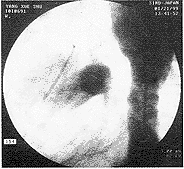

关键词:,图1主动脉弓降部造影(栓塞前),图2主动脉弓降部靠边影(栓塞后)